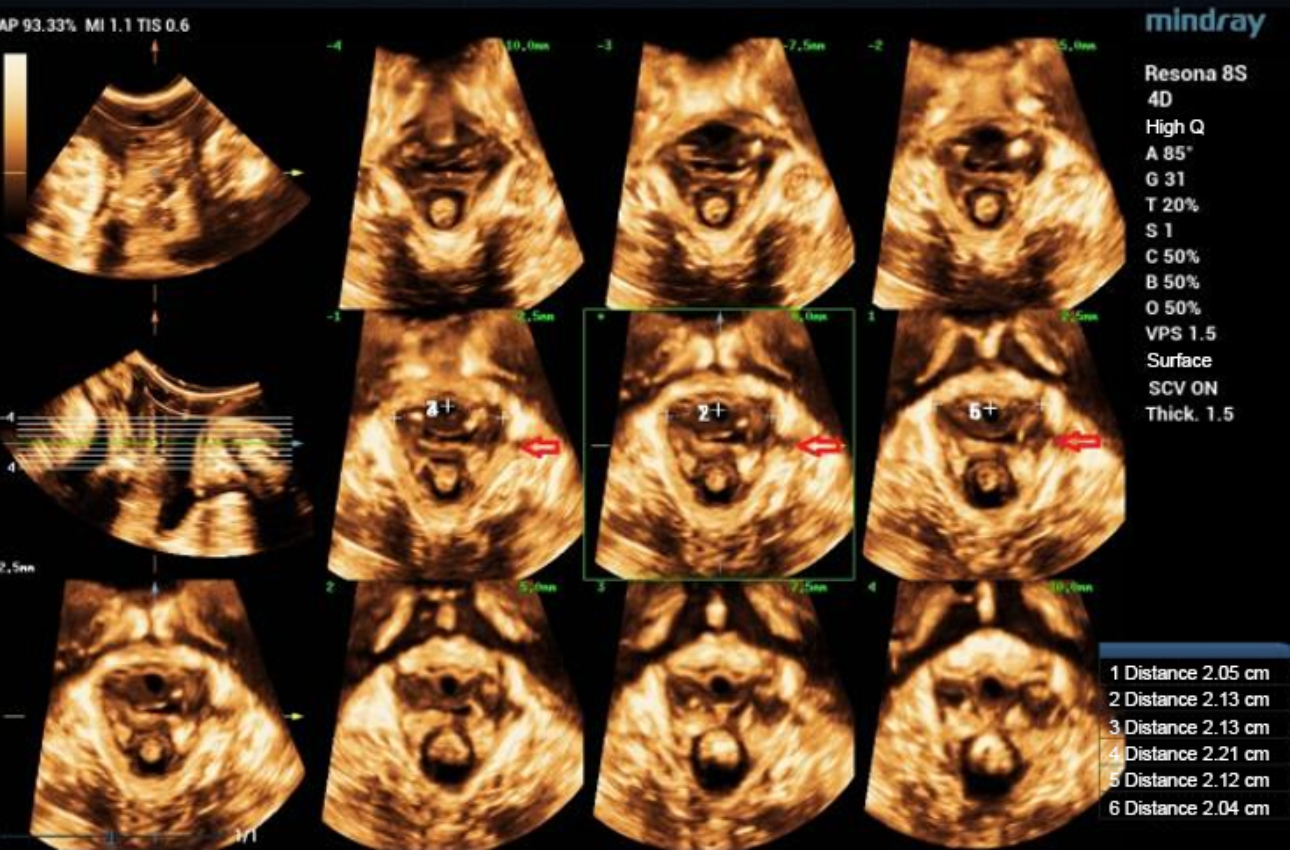

형상 2. 정상 levator ani 근육의 Ipage+영상은 3x3모드를 채택하고, 양쪽 levator ani 근육의 균일한 반향과 대칭되는 모습을 보여줍니다. 가운데 3개의 이미지들은 각각 2.5mm의 레이어 간격으로 pubic symphysis의 열림과 닫힘, 그리고 닫힌 상태를 보여줍니다.

형상 4. 좌측 avulsion의 Ipage+ 이미지